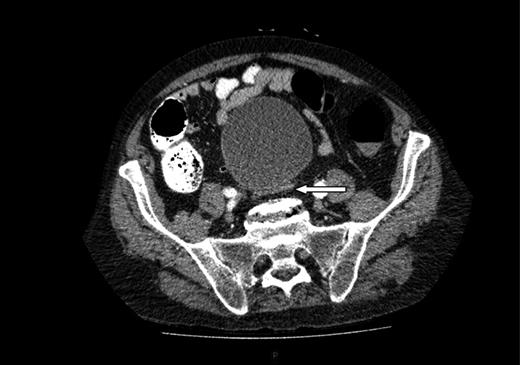

A computed tomography (CT) of the abdomen and pelvis was performed. This showed a grossly distended urinary bladder and compression of the sigmoid colon against the sacral promontory causing bowel obstruction (Figs 1 and 2, respectively) as well as a 4.9 cm abdominal aortic aneurysm without any signs of a rupture (Fig. 3). The plan was to consult our vascular colleagues regarding management of the AAA once the obstruction had settled.

Further image of the same CT scan showing compression of the sigmoid colon against the sacral promontory (see arrow) behind the distended bladder.